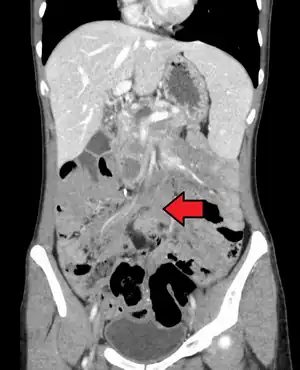

| Desmoid tumor as seen on CT scan | |

Aggressive fibromatosis or desmoid tumor is a rare condition. Desmoid tumors arise from cells called fibroblasts, which are found throughout the body and provide structural support, protection to the vital organs, and play a critical role in wound healing. These tumors tend to occur in women in their thirties, but can occur in anyone at any age. They can be either relatively slow-growing or malignant. However, aggressive fibromatosis is locally aggressive and can cause life-threatening problems or even death when they compress vital organs such as intestines, kidneys, lungs, blood vessels, or nerves. Most cases are sporadic, but some are associated with familial adenomatous polyposis (FAP). Approximately 10% of individuals with Gardner's syndrome, a type of FAP with extracolonic features, have desmoid tumors.[1]

Desmoid tumors may be classified as extra-abdominal, abdominal wall, or intra-abdominal (the last is more common in patients with FAP). It is thought that the lesions may develop in relation to estrogen levels or trauma/operations.